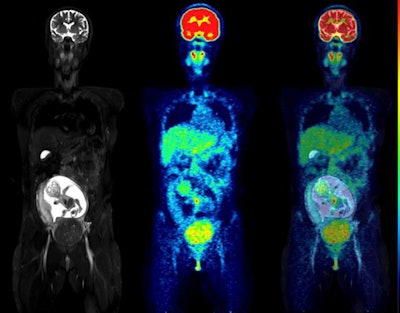

All fetuses were visible in detail on the MRI scans, which allowed the delineation of their body contours. F-18 FDG activity was unevenly distributed in the fetal body. The hearts were generally visible, while the brain showed low uptake, the results showed.

The women were injected with approximately 4 MBq/kg of F-18 FDG (average injected activity, 213 ± 52 MBq) prior to imaging. In part, the fraction of injected activity concentrated by the fetus was derived from manually drawing regions of interest on the MRI slices.

In this study, Zanotti-Fregonara and Japanese colleagues analyzed data from 11 women who underwent F-18 FDG PET/MRI scans (Biograph mMR, Siemens Healthineers) at Fukushima Medical University Hospital for cervical cancer staging during the first two trimesters of pregnancy. F-18 FDG dose estimates were calculated using a voxel-based methodology Zanotti-Fregonara at al proposed in a 2016 study that used anthropomorphic phantoms.